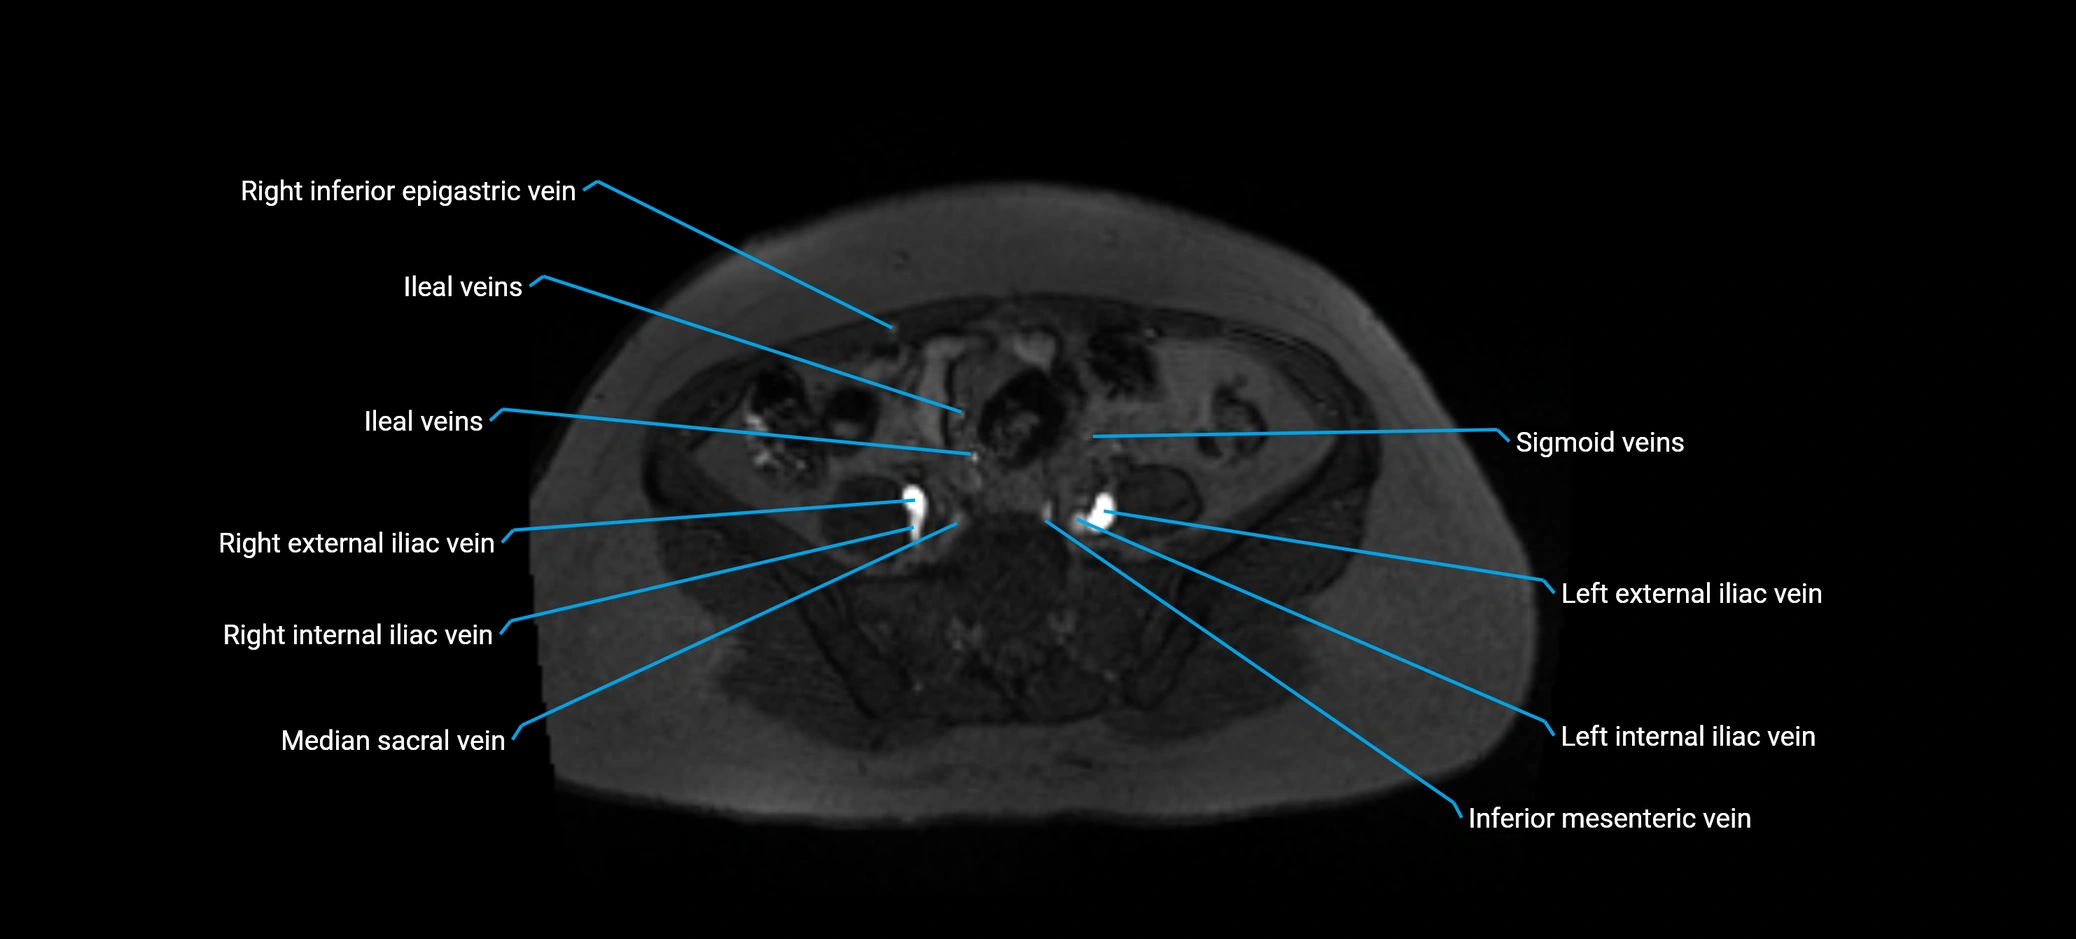

MRI image

image